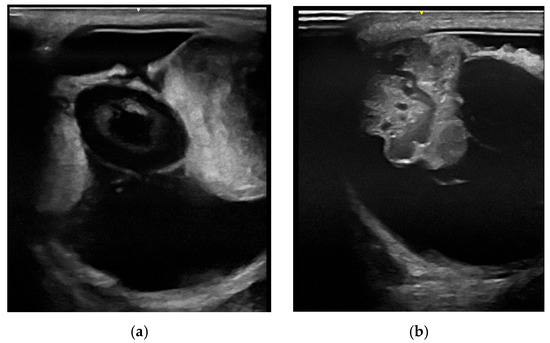

Intraocular Tumors in Horses: Diagnosis, Tumor Classification, Oncologic Assessment and Therapy

Intraocular neoplasia in horses is rare and only few case reports and small case series exist. Intraocular neoplasia has various clinical signs and includes important differential diagnoses in ocular disease. This narrative review of the current literature aims to provide a clinically relevant overview and classification of intraocular tumors in horses and adds a comparative oncological perspective concerning diagnosis, treatment and future considerations. The available clinical and imaging examination techniques allow for a reliable and differentiated investigation of the tumor, even in the standing horse, using high-frequency ultrasound or optical coherence tomography, which have gained importance in equine ophthalmology. Sectional imaging techniques, in particular computed tomography, are suitable for the examination of the peribulbar, retrobulbar and orbital structures. Differentiated diagnostics including precise tumor staging (TNM: tumor, node, metastasis) are essential for a general prognostic and therapeutic assessment. The embryologic and anatomic tissue origin of the neoplasm is the basis for clinicopathologic classification. Medulloepithelioma and uveal melanocytic neoplasia are the most common intraocular tissue formations occurring in horses. Whereas melanocytic neoplasia of the iris can be treated surgically, neuroepithelial tumors regularly lead to bulbus extirpation. Other primary intraocular neoplasms are sporadically reported, as well as intraocular metastasis of systemic neoplasia. Chemotherapy and radiation therapy are not currently used to treat intraocular neoplasia in horses and need to be further investigated, especially regarding the latest developments in human and small animal medicine. In addition, horses and dogs may serve as models for human oncologic research. Full article

Show Figures

Figure 1